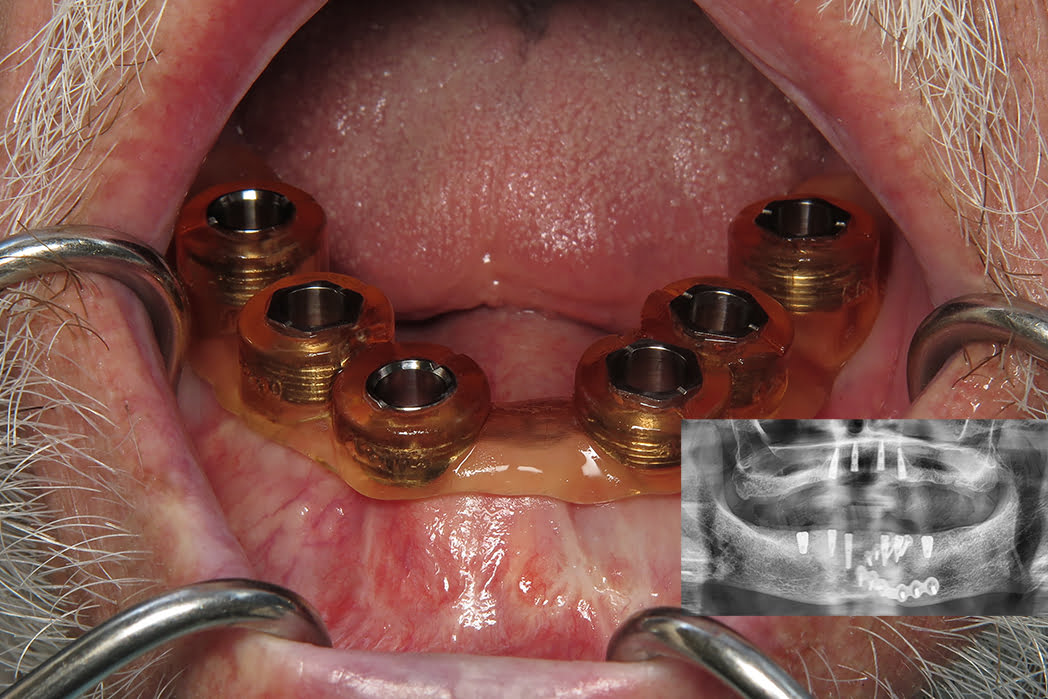

We came up with a plan, 4 implants on the maxillary arch for a future LOCATOR R-Tx overdenture and 6 implants on the mandibular arch for a future LOCATOR F-Tx fixed bridge. We came up with the 6 implants and fixed option because the patient was nervous about removing the fixation hardware and a tissue-supported overdenture would cause tissue impingement on the frame. With a fixed bridge, we could suspend it over the top with little pressure on the ridge.

After placing the maxillary implants, I move onto the mandibular arch. Since we have to work around some of the plating hardware, I placed the implants in creative positions. Ideally I would want to see implants in the #19, 21, 22, 27, 28, 30 positions for a fixed prosthesis, I did have to wiggle around in that left side. I got the implants in position so that way I was keeping clear of the screws and plating. Guided surgery will allow me to navigate this tricky position because if I was placing implants free hand, I would have to elevate huge flaps and likely need to remove the plating before surgical procedures.

After flap elevation, the guide was palced back and the second osteotomy procedure completed through the guide. The guide removed and conventional osteotomies performed freehand and implants placed. Chromic gut sutures were placed to close the surgical site.

After the mandibular implants were placed, maxillary implant procedures were completed, placing 4.2×11.5 Paltop Advanced Classic implants. The patient was thrilled with the result and is very much looking forward to his completed prostheses!

This case illustrates the benefit of using guided implantology as traditional surgical procedure would be quite invasive. As a result, I was able to keep my surgical site clean, minimally invasive procedures completed, and also ensure that my implants are in sufficient positions of bone volume and prosthetic positions to ensure health of the implants and future restorations!